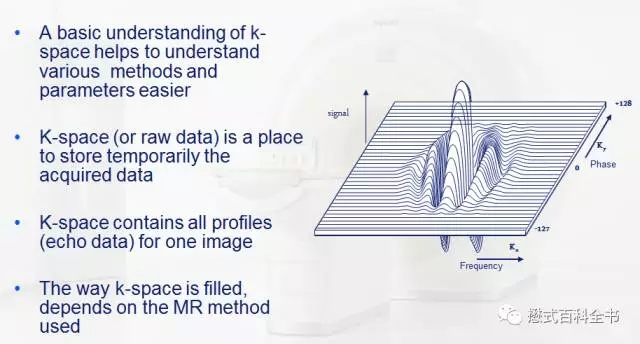

K空间的概述

讲了这么多,大家只需要简单的记住,K空间就是储存磁共振原始数据的空间,可以通过K空间的原始数据进行非常复杂的数据后处理,得到磁共振图像。

图3:上图是一个K-space的示意图

上图是一个K空间的示意图,我们知道磁共振需要需要对质子进行空间定位,会用到不同方向的梯度磁场。

如果以一个2D采集为例,首先通过层面选择梯度,激发某一固定的一层,然后在通过相位偏码梯度和频率编码梯度来对该层的质子进行空间定位。

一个二维平面,我们可以把它分为两个正交方向,即:Ky(相位编码方向)和Kx(频率编码方向)。一个TR周期,把采集的一次信号填充到K空间中,在相位编码方向上,有多少个步级,我们就需要填充多少个相位编码线,最后把K空间数据填充完毕,进行图像后处理形成磁共振图像。